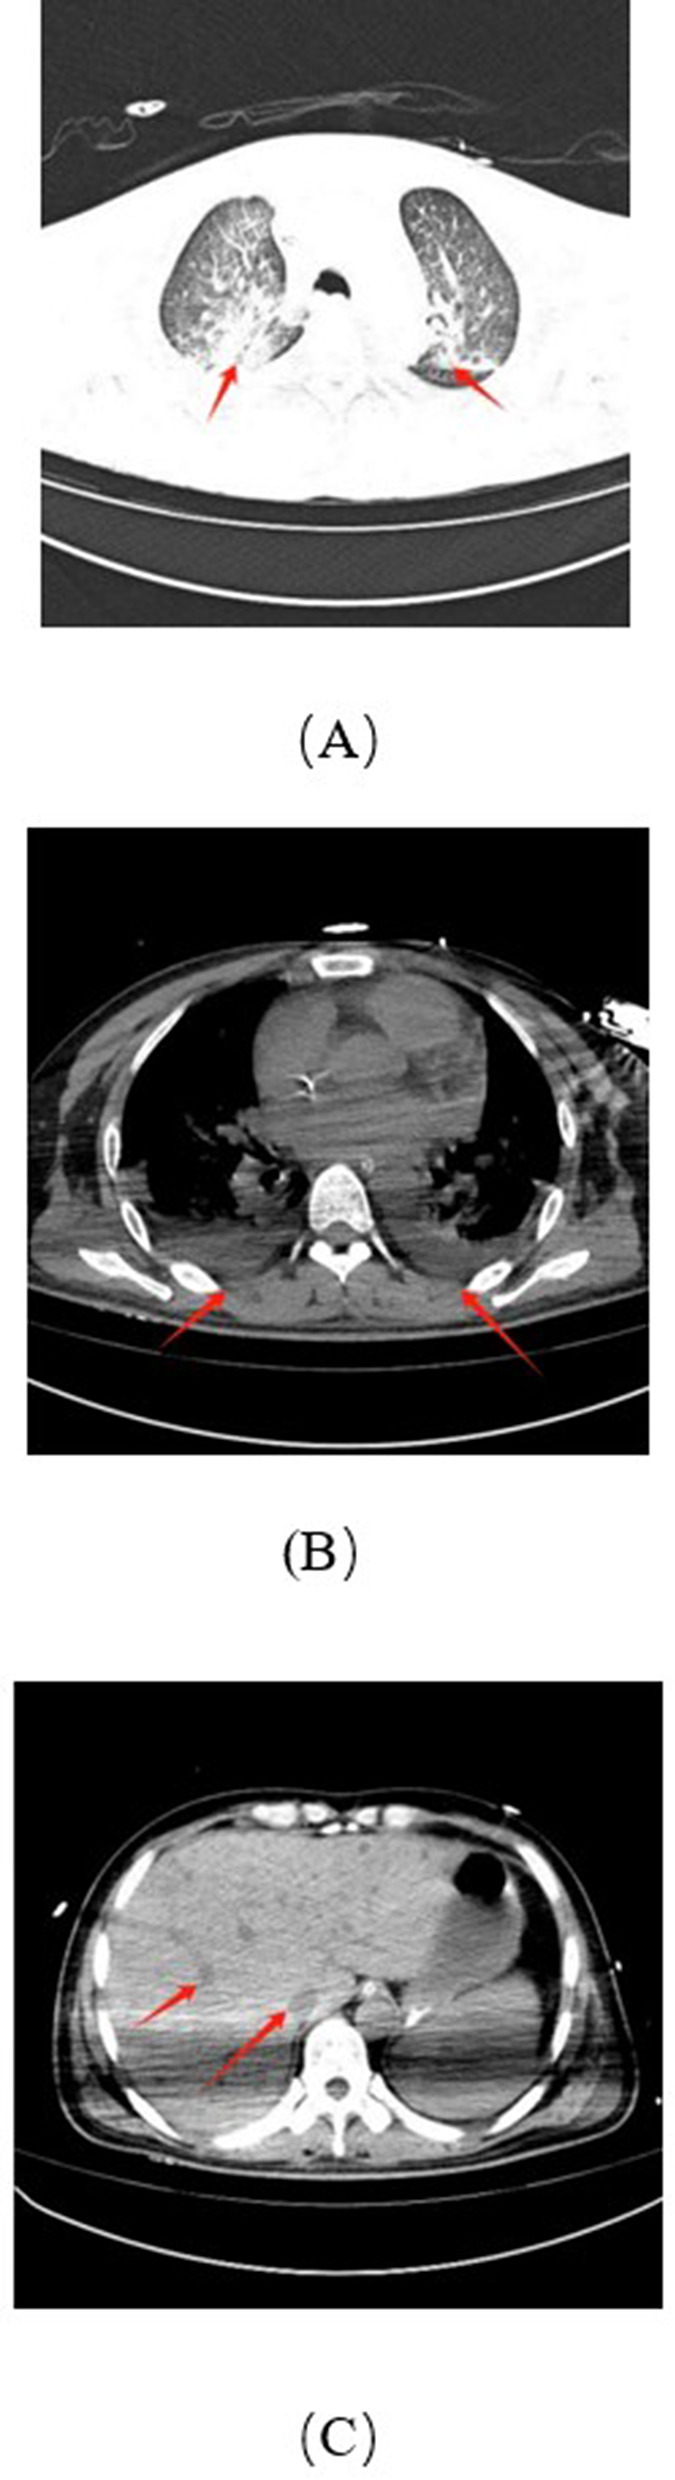

Yersinia pseudotuberculosis is a Gram-negative bacterium of the family Yersiniaceae, primarily transmitted via the gastrointestinal tract. Progression to sepsis is uncommon, and the combination of septic shock and splenic infarction is exceedingly rare. We report a 40-year-old male who initially presented with fever, abdominal pain, and distension, which rapidly progressed to sepsis and multi-organ dysfunction. Definitive diagnosis of Y. pseudotuberculosis infection was established by blood culture and metagenomic next-generation sequencing, supported by imaging evidence of splenic infarction. The patient was managed with stepwise antimicrobial regimens (including piperacillin-tazobactam, meropenem, levofloxacin, linezolid, and daptomycin), plasma exchange, continuous renal replacement therapy, and organ function support. Following comprehensive treatment, the patient recovered and was discharged in stable condition. This case highlights the importance of considering Y. pseudotuberculosis in atypical sepsis presentations and demonstrates that timely diagnosis and multidisciplinary management are crucial to improving outcomes in such rare and life-threatening infections.